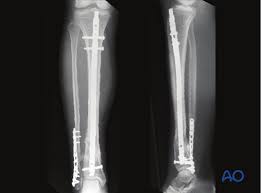

This nail comes in diameters from 8mm to 12mm, with lengths spanning 255mm to 375mm in 15mm increments, giving options for adult and pediatric cases alike. A smart 10.5° proximal bend eases entry via suprapatellar or infrapatellar portals, while full cannulation lets guide wires glide through for reamed or unreamed techniques. Multi-directional locking holes shine: two medio-lateral (ML) for compression or dynamization, plus an anterior-posterior (AP) for distal grip, all accepting self-tapping 3.9mm, 4.7mm, or 4.9mm bolts. End caps in 0-15mm lengths seal the proximal end, blocking tissue ingrowth to simplify future removals.

Start with the patient supine, knee flexed 90 degrees, and a precise patellar tendon split for safe entry—suprapatellar portals cut malalignment risks by hugging the natural tibial bow. Ream 1-1.5mm over nail size, pass a ball-tip nitinol wire, then drive the nail under fluoro to span the fracture by 2-3cm distally. Lock proximally with a jig for ML screws, distally freehand through perfect circles to avoid over-reaming. For unstable comminuted fractures, static mode holds rigid; dynamic slots allow controlled slide in transverse gaps. Total op time? Typically 60-80 minutes, with minimal soft-tissue trauma.

Titanium's biocompatibility slashes infection odds below 2%, and its low modulus matches bone to prevent stress shielding. Angular stability from ML/AP combos outperforms single-plane designs, boosting union rates to 97% in 12-16 weeks. Compared to plates, smaller incisions preserve quads and preserve blood supply for faster callus. Patients bear partial weight day three, full by week eight—no bulky externals or cast atrophy. Removal? Straightforward after 18 months, with rare ingrowth thanks to end caps.